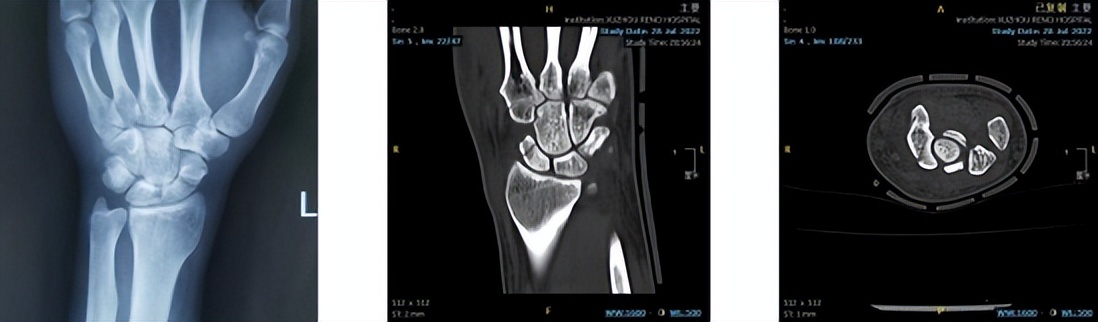

近日,王先生在下楼梯时不慎摔倒,摔倒时他下意识地用左手撑了一下,起身后就发现左手腕开始肿胀、疼痛,在当地医院行X线检查后提示:考虑舟骨骨折,因肿胀疼痛不缓解,为进一步明确诊断、治疗,前往徐州仁慈医院就诊,经CT检查确诊为左腕舟骨骨折。

舟骨骨折是骨科急诊、门诊中较为常见的疾病,其发病率占腕骨骨折的 60%-80%,是腕部骨折中仅次于桡骨远端骨折,多由运动性损伤所致。由于舟骨本身特殊的血供及骨折部位的不同,导致其延迟愈合率、不愈合率和缺血坏死率都很高,尤其对于急性腰部完全骨折和近极骨折,单纯的石膏外固定往往使不愈合率大大增加,并常引发舟骨骨不连、腕关节进行性塌陷(scaphoid nonunion advanced collapse,SNAC)导致腕关节运动功能障碍,因此被称为“令人尴尬但非常重要的小骨头”。由于腕舟骨体积小、解剖结构复杂,三维立体结构特殊,这种手术对医生的要求非常高,如何将Herbert螺钉精准置于舟骨轴线位置是所有骨科医生面临的挑战。